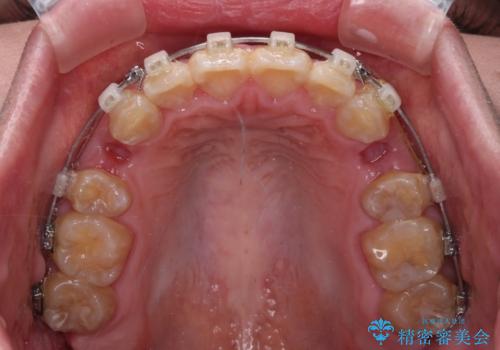

- クリアブラケット

- 2年4ヶ月

- 口元の閉じにくさと、前歯のでこぼこの歯並びを気にして来院された患者様です。

口元を積極的に引っ込めるために、上下左右の小臼歯計4本を抜歯することとしました。

4本の歯を抜歯したことで、飛び出していた口元が引っ込み、横顔が大きく改善されました。